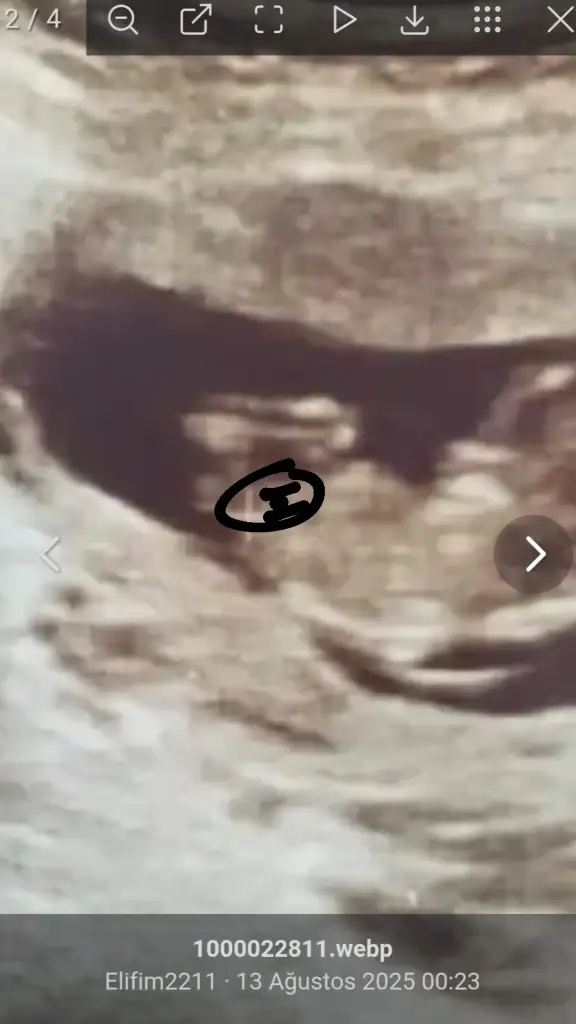

Kız gördüm sanki, sağlıcakla gelsinArkadaşlar 12+5 ultrason fotoğraf ı kız mı erkek mı sızce

Bir çoğunda ölçüm çizgisi o kısıma denk gelmiş ama, bir tanesinde kız gördüm sanırım, sağlıcakla gelsinMerhaba benimde yorumlarmisiniz rica etsem 11+1

Ben de kız gördüm ama annenin içine doğan da olabiliyor çoğunlukla, hayırlısıyla sağ salim doğsunlar inşallahAllah razı olsun cnm benim bunu erkek bekliyordum kısmetİKİZLER normalde çif yumurta ikizi diğeri kesin kız dedi buna da kız gıbı küçük daha dedı belli olmuyor dedı belki siz tahmin edersiniz cinsiyeti dıye atmak istedim size kıza benzıyor dedı erkek hissediyorum ama ben ya kısmet

Aaa çok sağolun ben hiç anlamıyorum Instagram da 5 kişiye sordum 4 kız dedi 1 erkek teoriye ve boyama işlemi ile bakanlar da oldu gönlümden geçen kız umarım doğrudur gördüğünüz ben anlamıyorum . Rica edecem eğer sizi yormayacaksam nerde gördünüz hangi fotoğraf da acbaBir çoğunda ölçüm çizgisi o kısıma denk gelmiş ama, bir tanesinde kız gördüm sanırım, sağlıcakla gelsin

Bakın işte burada 3 çizgiMerhaba benimde yorumlarmisiniz rica etsem 11+1

Aaa çok sağolun ben hiç anlamıyorum Instagram da 5 kişiye sordum 4 kız dedi 1 erkek teoriye ve boyama işlemi ile bakanlar da oldu gönlümden geçen kız umarım doğrudur gördüğünüz ben anlamıyorum . Rica edecem eğer sizi yormayacaksam nerde gördünüz hangi fotoğraf da acba

Çok teşekkür ediyorum sağolunBakın işte burada 3 çizgiAma henüz yeni yeni oluştuğu için yanılma payı olabiliyor tabiki

İlerleyen haftalarda ayrıntılı ultrasona gircem yine atsam bakabilir misinizBakın işte burada 3 çizgiAma henüz yeni yeni oluştuğu için yanılma payı olabiliyor tabiki